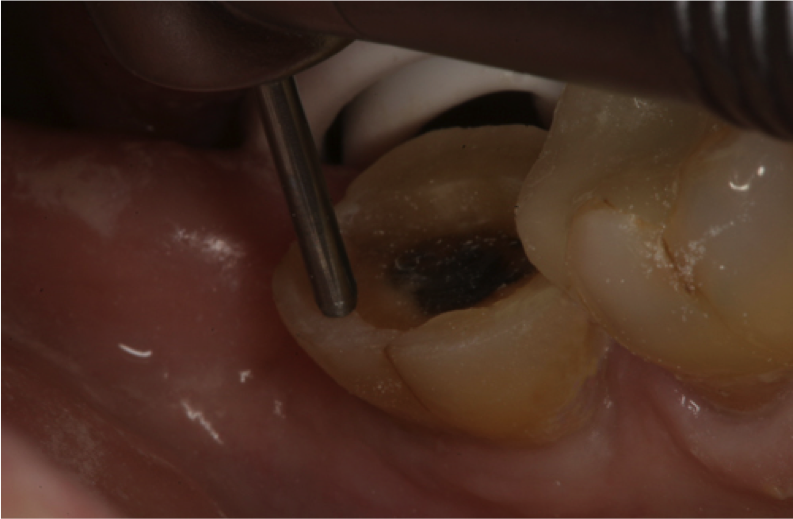

Fig. 6  Acid-etching the preparation to deep etch the enamel and clean the dentin prior to application of universal adhesive.

Figure 6

At the insertion phase, the entire preparation is acid-etched (Figure 6). This provides a deep etch pattern in the enamel and also cleans the resin-coated dentin. Universal adhesive is then applied to the entire preparation, and depending on the manufacturer’s instructions, light-cured or not. The restoration is then inserted and light-cured for few seconds, first on the buccal side and then on the lingual, while holding the restoration in place (Figure 7). Floss is inserted through the contacts, and any excess adhesive is removed before final light-curing (Figure 8). This alternative selective-etch technique provides immediate dentin sealing. It creates better self-etch dentin adhesion because it does not deplete the available calcium. It produces a better etch-and-rinse enamel etch pattern without accidental dentin demineralization, and it can be used for direct or indirect restorations.